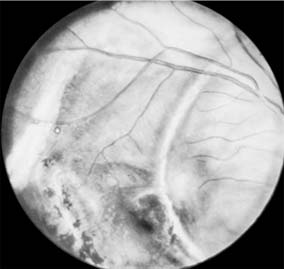

INTRAOCULAR FOREIGN BODIES (Figure 19-5)

Figure 19-5

Figure 19-5: Ophthalmoscopic view of intraocular metallic (iron) foreign body in vitreous.

Foreign bodies that have been identified and localized within the eye must be removed whenever possible. Particles of iron or copper must be removed to prevent later disorganization of ocular tissues from toxic degenerative changes (siderosis from iron and chalcosis from copper). Some of the newer alloys are more inert and may be tolerated. Other kinds of particles, such as glass or porcelain, may be tolerated indefinitely and are usually better left alone.